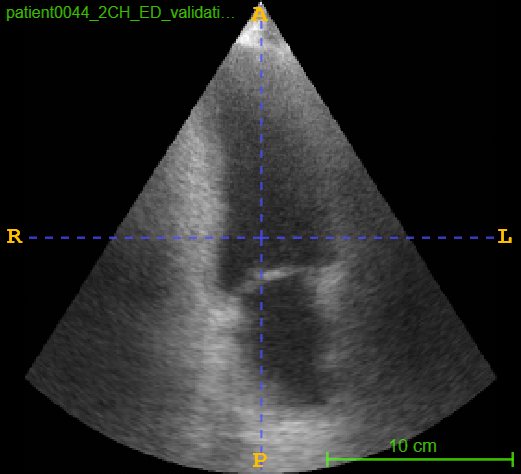

4.3 CAMUS Echocardiogram View Classification

After investigating the issue of synthetic simplicity in the digit classification task, we demonstrate the phenomenon on a representative medical imaging task of cardiac view classification from echocardiographs. We utilized the publicly available echocardiography dataset "Cardiac Acquisitions for Multi-structure Ultrasound Segmentation" (CAMUS) [8] for this experiment. The CAMUS dataset comprises four types of cardiac views from over 500 subjects: two-chamber end-systolic (2CH ES), two-chamber end-diastolic (2CH ED), four-chamber end-systolic (4CH ES), and four-chamber end-diastolic (4CH ED). We focused on the "4CH ED" and "2CH ED" classes in the CAMUS dataset for classification task. Figure 2 shows real and synthetic samples of 4CH ED and 2CH ED echocardiogram views.